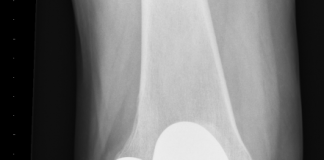

Orthopeden plaatsen 3D-geprinte onderdelen knieprothese

Orthopedisch chirurgen Louis Marting en Martijn van Dijk van het St. Antonius Ziekenhuis in Utrecht/Nieuwegein hebben voor het eerst 3D-geprinte onderdelen van een knieprothese...